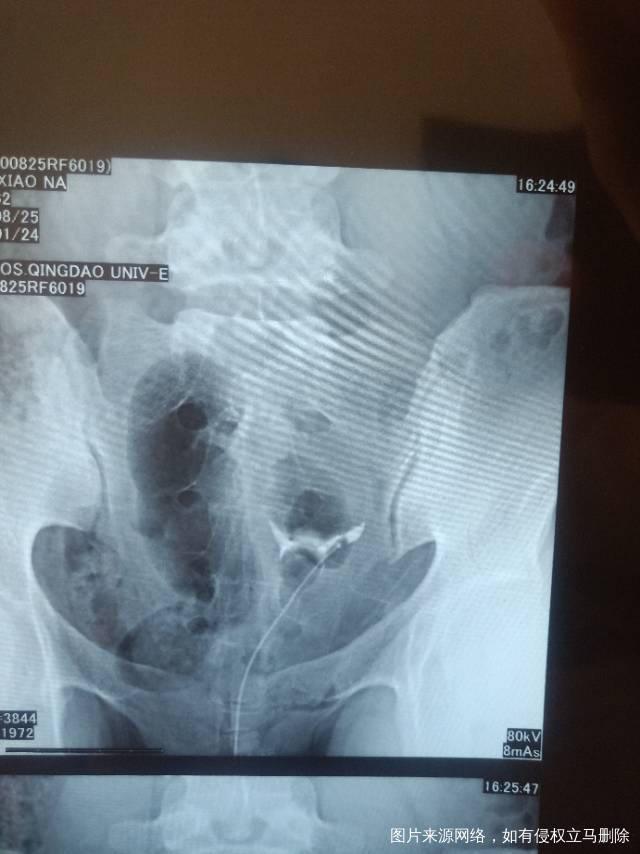

请问医生我这个造影有没有输卵管积水呀影不影响